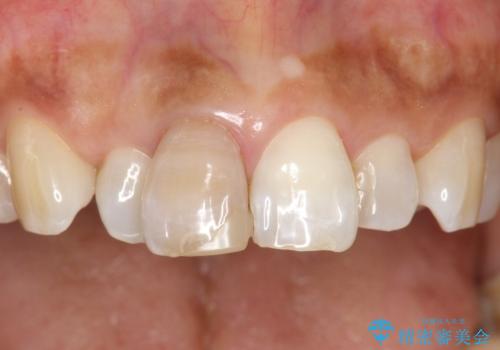

- 右上の前歯が左隣の歯に比べて色が暗いのが気になるとのことで来院されました。

右上1は根管治療がされており、神経がないため歯自体も変色していること、詰め物の色も変色していることをふまえ、オールセラミッククラウン(スペシャル)による治療を行うことになりました。